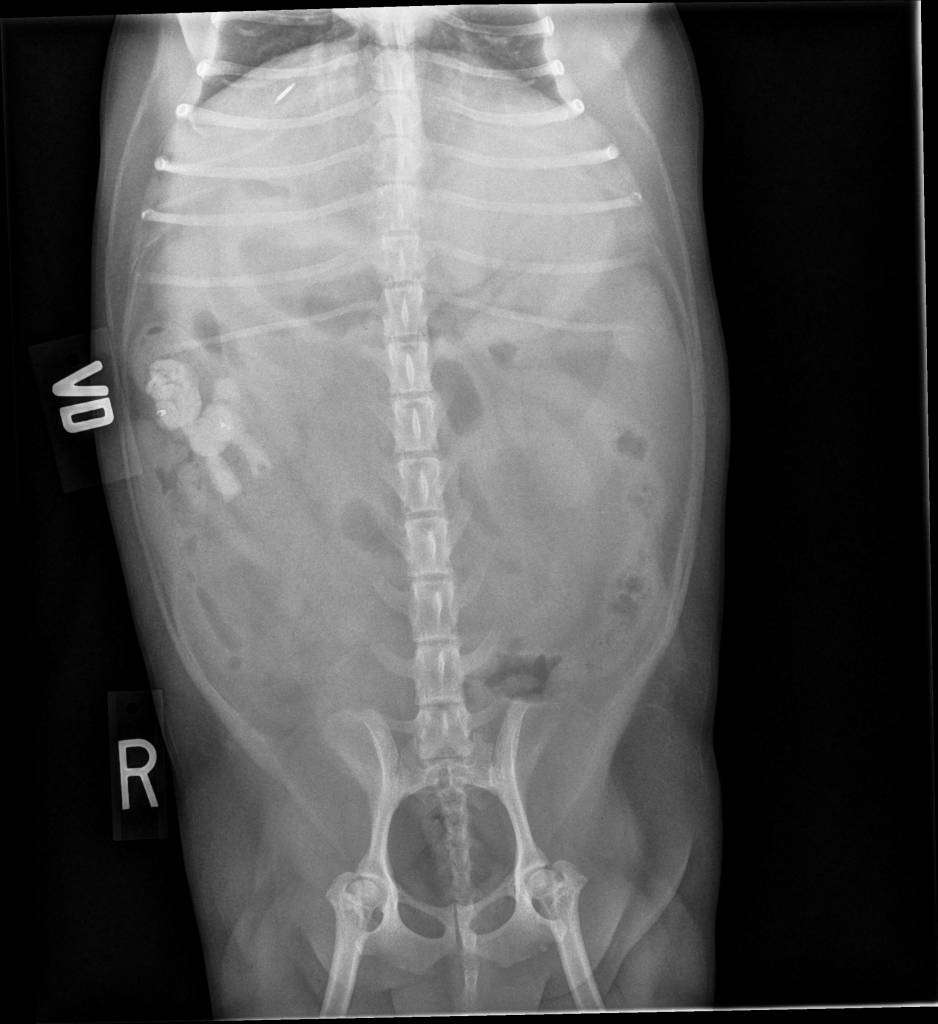

They Ate What?! X-ray Contest 2018They ate this: Check out the winner, runners-up, and honorable mentions October 1, 2018 < Previous Entry Next Entry > Pages: 1 2 3 4 5 6 7 8 9 10 11 12 13 14